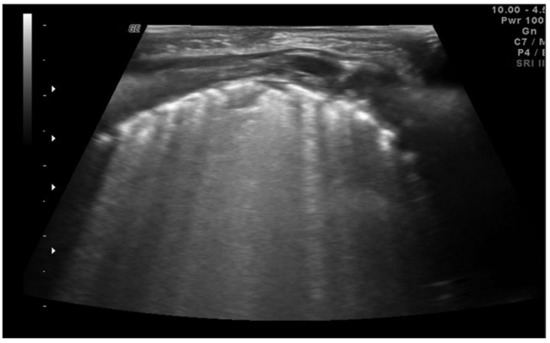

Neonatal respiratory distress syndrome (NRDS) is characterized by a functional and structural immaturity of the lung resulting in respiratory distress that appears at birth. The ultrasound findings of NRDS are represented by coalescent B-lines, diffuse and symmetrically distributed in both lungs. These lines are due to the presence of fluid in the interstitial or alveolar compartment, and generally, their number correlates with the severity of the disease, up to “white lung” in the most severe cases. The pleural line appears irregular, poorly defined and thickened. In addition, small areas of hypoechogenic subpleural consolidation can often be observed, especially in the posterior lung fields (Figure 4) [21].

Neonatal respiratory distress syndrome (NRDS). Coalescent B-lines, irregularity of the pleural line and subpleural consolidation are visible.